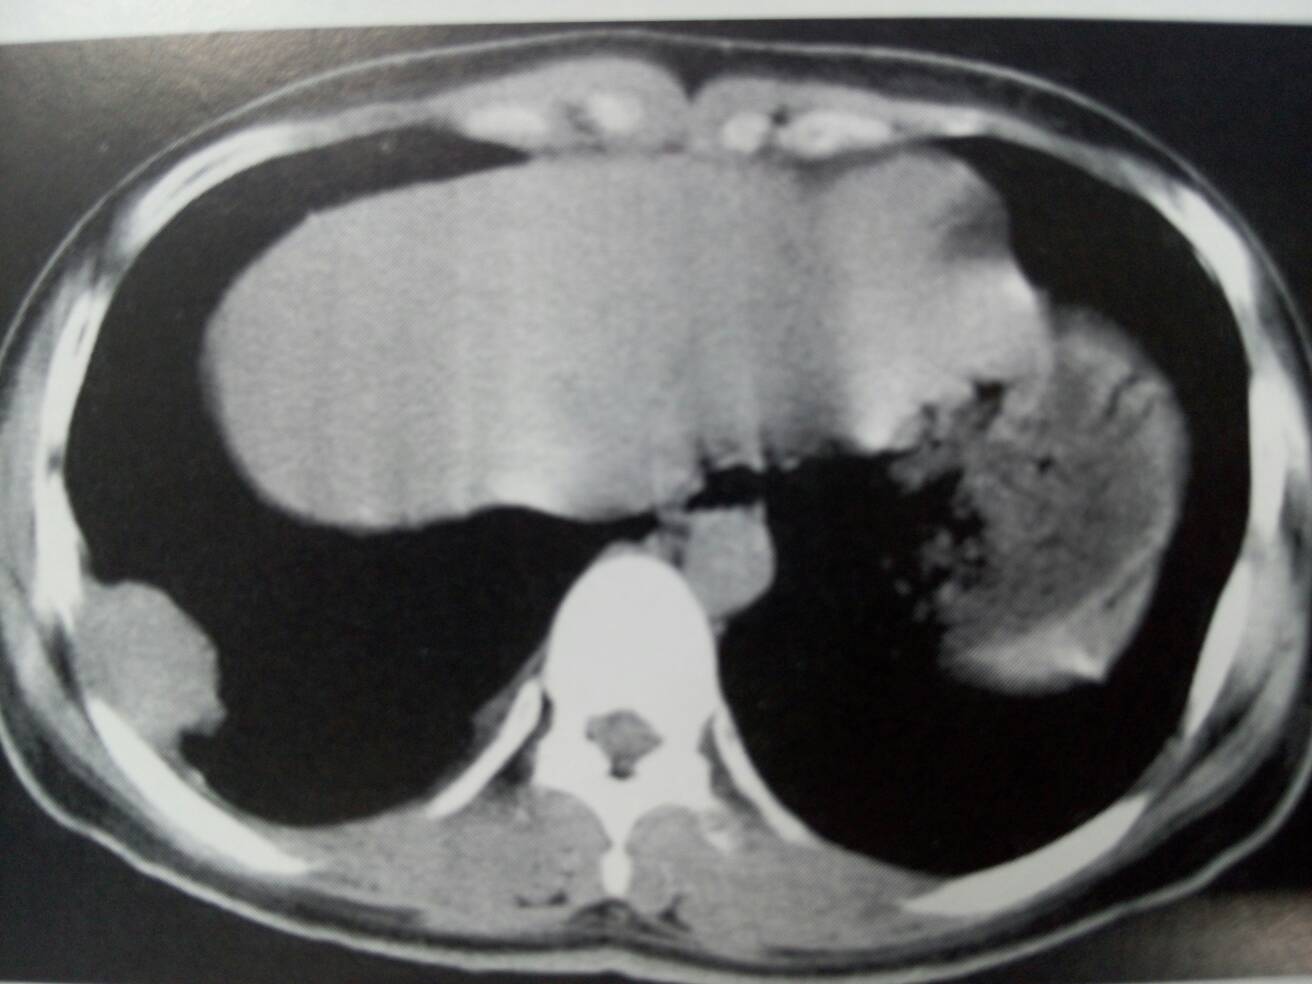

胸壁纤维瘤。右侧胸膜紧贴胸壁的包块影,边缘光整,密度均匀。